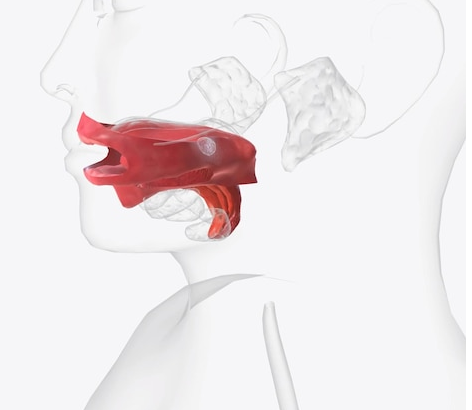

Неделя 1. ВВЕДЕНИЕ В ПИЩЕВАРИТЕЛЬНУЮ СИСТЕМУ. ПОЛОСТЬ РТА.

Глоточный аппарат и его производные. Особенности слизистой оболочки ротовой полости. Развитие и строение губы, языка, зуба. Лимфоидная ткань: строение небной миндалины. Малые слюнные железы